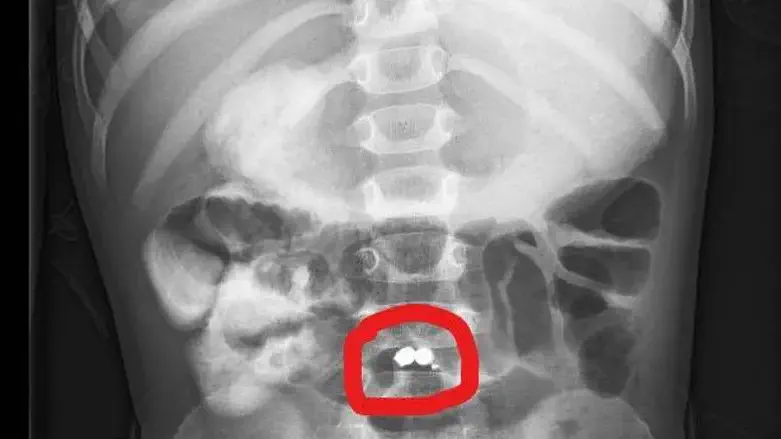

בבדיקות שנערכו במחלקה לרפואה דחופה לילדים התברר שכדורי מגנט שבלע הפעוט יצרו חורים במעי הדק וגרמו לזיהום מסכן חיים כתוצאה מכך שתוכן של מערכת העיכול דלף לחלל הבטן.

ד"ר מרק ארקוביץ, מנהל המחלקה לכירורגית ילדים אמר כי "הילד הגיע למחלקה לרפואה דחופה בילדים כשהוא סובל מכאבי בטן, חום, בטן נפוחה ומאוד רגישה. בבדיקות ההדמיה נראו שני כדורי מגנט שנצמדו משתי דפנות המעי ויצרו שלושה חורים. מדובר במצב מסכן חיים, שכן חורים במעיים עשויים לגרום לדליפה של תוכן המעי לחלל הבטן, לזיהומים ואף למוות. לכן, המטופל נכנס לניתוח חירום שביצע בהצלחה רבה ד"ר מרואן אליאס, רופא בכיר במחלקה כירורגית ילדים. ד"ר מרואן הוציא את המגנטים ותפר את החורים שנוצרו".